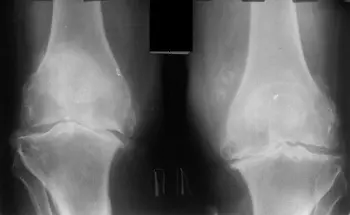

এই ছবিগুলো দেখো। সঠিক ছবিতে, জয়েন্টের জায়গা নেই, হাড়গুলো একে অপরের সাথে ঘষছে, যার ফলে তীব্র ব্যথা হচ্ছে। আর এই প্রক্রিয়া বন্ধ করা খুব কঠিন! কয়েক বছরের মধ্যে, ব্যক্তিটি অক্ষম হয়ে যাবে এবং নিজের যত্ন নিতে পারবে না।

এই সবই তরুণাস্থি টিস্যুকে নরম করে, জীর্ণ করে এবং পাতলা করে। প্রতিটি নতুন নড়াচড়ার সাথে, তরুণাস্থি জীর্ণ হয়ে যায় এবং বিকৃত হয়ে যায়, হাড়গুলি একে অপরের সাথে ঘষতে শুরু করে, যার ফলে অসহনীয় ব্যথা হয়।

রিউমাটয়েড আর্থ্রাইটিস এবং অস্টিওআর্থ্রাইটিস রোগ শুরু হওয়ার 3-5 বছরেরও কম সময়ের মধ্যে অক্ষমতা সৃষ্টি করতে পারে এবং আয়ু 15-20 বছর কমিয়ে দিতে পারে!